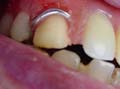

二月二十四日 金属支台

左上顎側切歯の歯根に装着する金属製の支台が出来上がった。

むし歯が進行し歯に穴があいてしまう。早期に治療すれば光重合レジンなどを用いて充填修復できるが、放置されさらにむし歯が進行して歯髄炎を起こしてしまったら抜髄しなければならない。抜髄後に根管充填するまで多くの治療時間を費やす。さらに根管充填したあとに形成して金属支台を作るための印象をする。金属支台は、多くの場合銀合金製でロストワックス鋳造法で作られる。金属支台が装着されたあとも幾多の処置が積み重ねられる。

金属支台が装着されるまでにも多くの知識と経験が必要でありそれを患者に「うまく」説明するにはさらに多くの知識と経験と「時間」が必要だ。患者が治りたいと願うことが医の基であるから「患者に説明する。」ということが医療の本質のであると思うが、その部分が正当に評価されているであろうか。